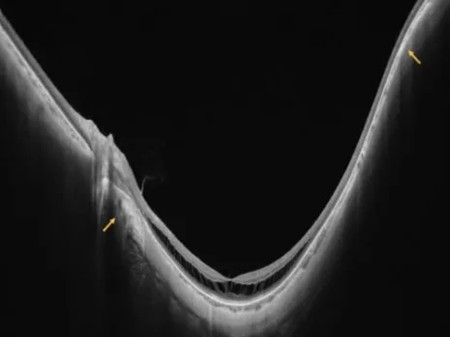

640 (8)_副本

黄斑劈裂